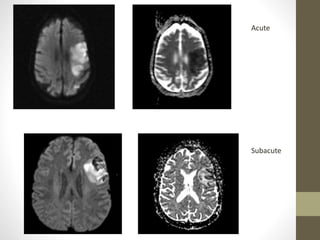

• The DWI and ADC maps – ischemic changes -within minutes to

few hours

• The signal intensity of acute stroke on DW images increase

during the first week after symptom onset and decrease

thereafter, but signal remains hyper intense for a long period

• The ADC values decline rapidly after the onset of ischemia and

subsequently increase from dark to bright 7-10 days later .

• This property may be used to differentiate the lesion older than

10 days from more acute ones (Fig 2).

• Chronic infarcts are characterized by elevated diffusion and

appear hypo or isointense on DW images and hyperintense on

ADC maps

Acute

Subacute